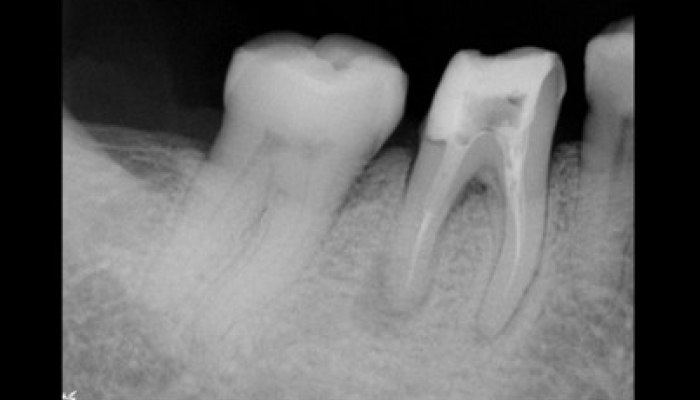

턱관절 머리뼈와 아래턱 사이에 있는 관절을 말합니다. 이러한 관절원판이 정상위치에서 있지 않거나, 마모되었을 때 턱관절 디스크가 발생하게 됩니다.

• 01 치아 교합 문제

치아가 잘 맞지 않거나,구강내 질환에 의해 턱관절의 운동에 이상이 생기면, 턱관절에 악영향이 가해집니다.